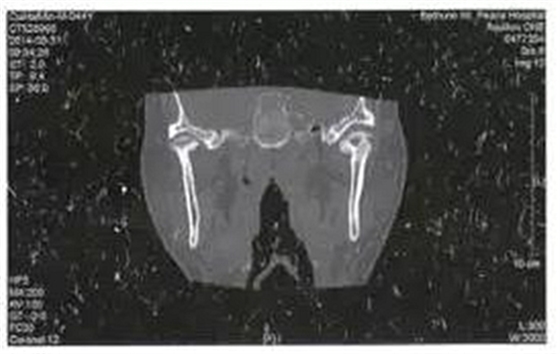

病例4,男,44歲。因左側(cè)耳前反復(fù)腫痛6月就診,檢查左側(cè)耳前區(qū)壓痛,軟組織腫脹不明顯,未見(jiàn)瘺管形成,張口度30mm,張口不偏斜,咬合關(guān)系可??趦?nèi)檢查未見(jiàn)病灶牙,無(wú)瘺管形成。全頜曲面斷層片檢查未見(jiàn)埋伏牙齒、囊腫等可能引起感染的病灶。CT掃描顯示左側(cè)髁突關(guān)節(jié)面成蟲(chóng)蝕樣破壞,中央部分為低密度病變(圖4)。

圖4左側(cè)髁突骨髓炎,關(guān)節(jié)面蟲(chóng)蝕樣破壞